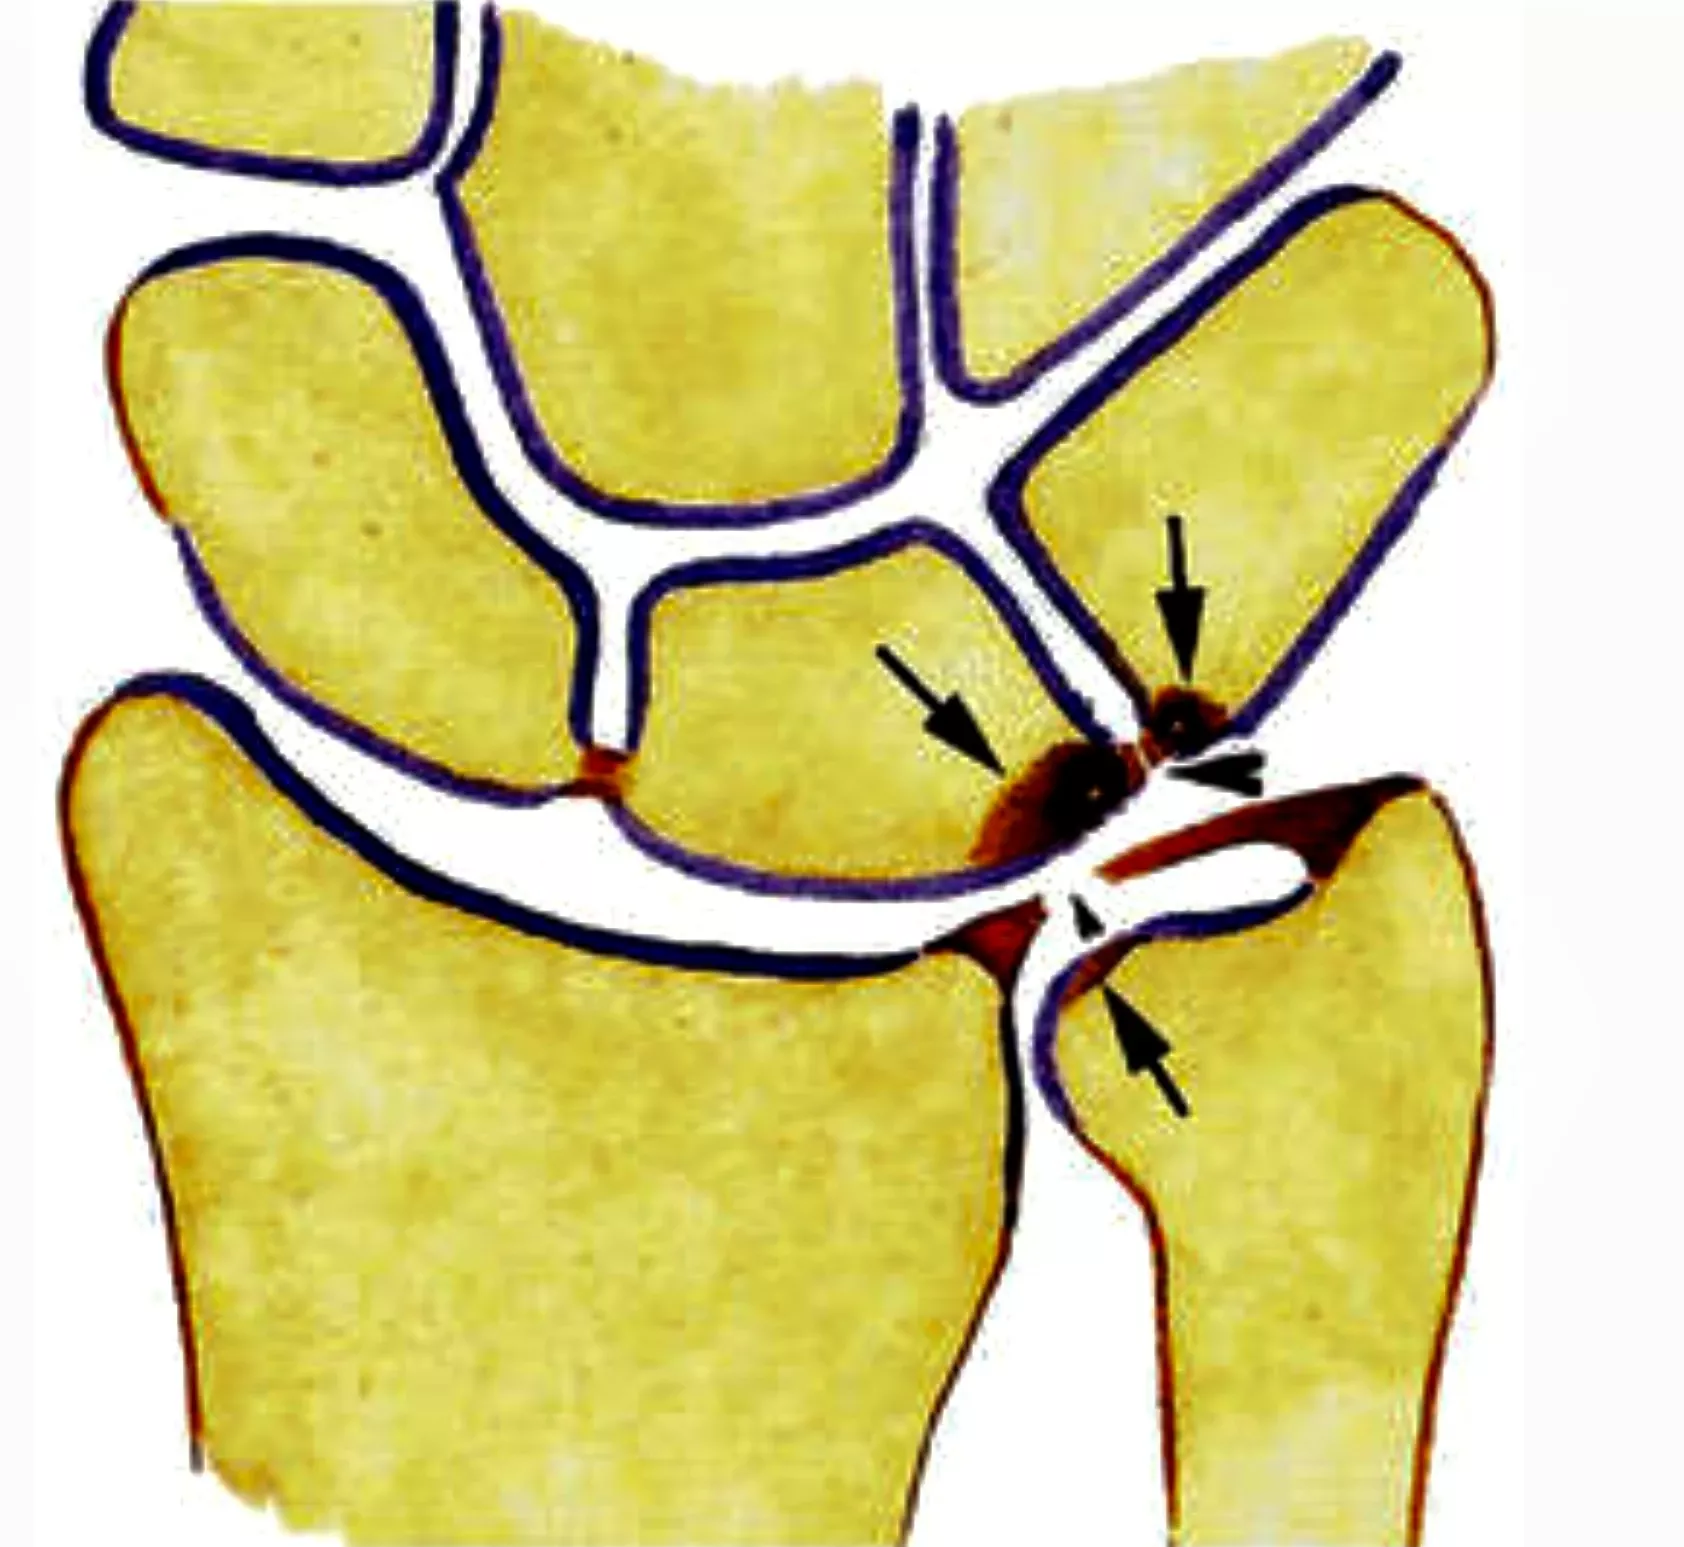

TFCC-letsel

Wat is het?

Het Triangular Fibrocartilage Complex (TFCC) is een soort meniscus van de pols. Het werkt als schokdemper tussen de onderarm en de polsbeentjes en bevat belangrijke stabiliserende ligamenten. Een TFCC-letsel kan ontstaan door:

- een val of plotse draaibeweging

- slijtage, o.a. door langdurige overdruk zoals bij een ulnair impactiesyndroom

Klachten

- Pijn aan de pinkzijde van pols en onderarm

- Pijn bij steunen, wringen of draaien

- Soms weinig klachten, afhankelijk van de grootte van de scheur